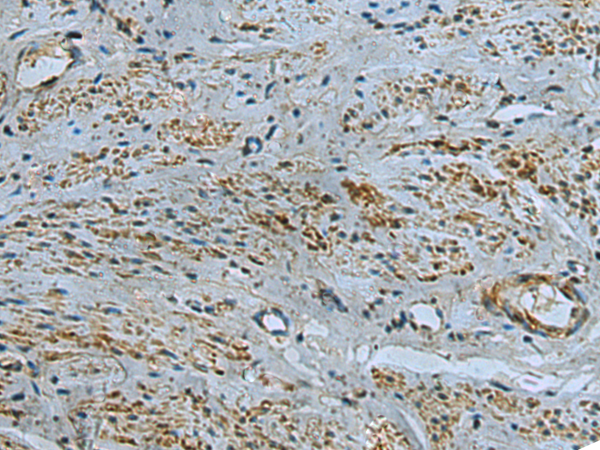

IHC positive control:

Human cervical cancer

IHC Recommend dilution:

50-100